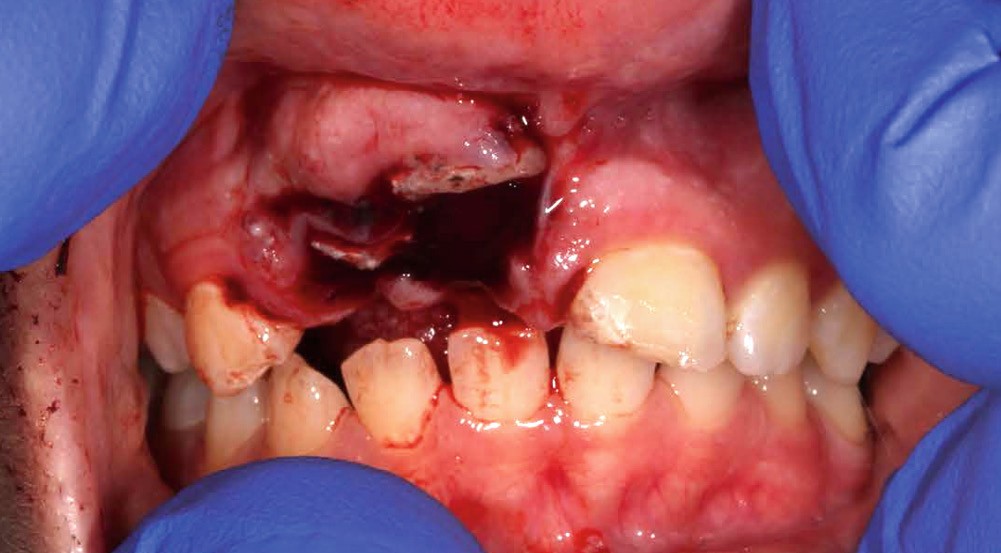

Yasmine, une adolescente de 14 ans et demi, en bonne santé générale, consulte en urgence vers 10h30, à la suite d’une chute s’étant produite le matin même en allant à l’école vers 8h. Les figures 1 et 2 montrent respectivement les vues cliniques et radiographiques. La mère nous rapporte un antécédent de trauma sur les incisives centrales, il y a quelques années.